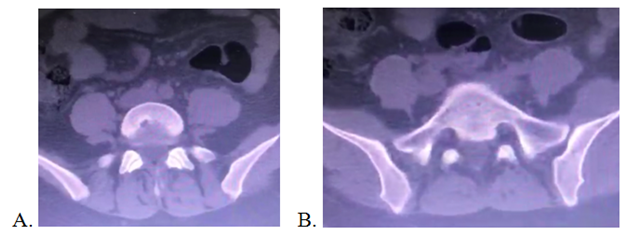

Magnetic Resonance Imaging (MRI) showed a perineural cyst extending from S2 to S4, remodeling posterior walls of S2 and S4 and enlarging sacral foramina of S2 to the right and S3 to the left, occupying almost entire vertebral canal (Figure 2).

Figure 2 MRI of sacral spine: giant epidural cist, from S2 to S4.